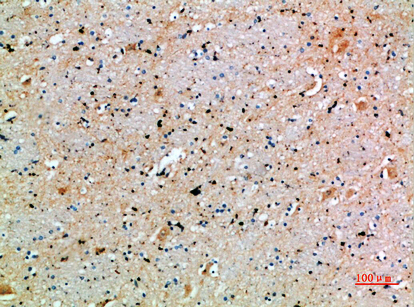

分类: 科研抗体货号: P43465别名: RN49018应用: IHC反应种属: Human